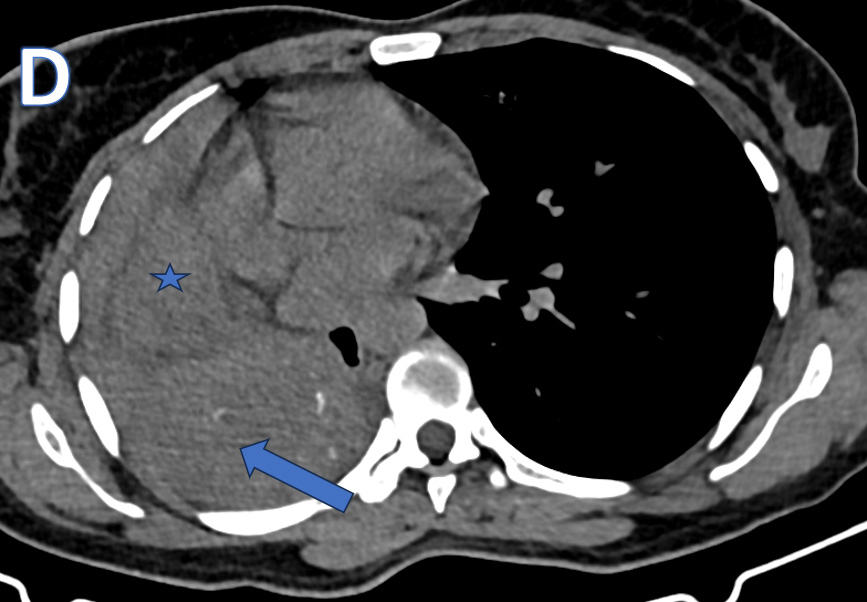

C – CORONAL CT THORAX

Ovoid heterogeneously isodense mass lesion with multiple tiny peripheral specks of calcifications in the right hemithorax with endobronchial extension.